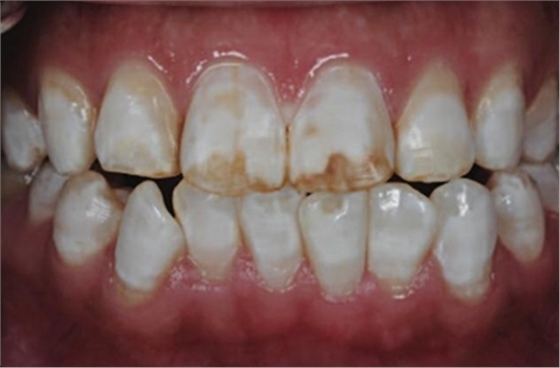

5、由于氟斑牙存在釉質(zhì)礦化不全等問題,家庭漂白兩周后,使用標(biāo)準(zhǔn)的樹脂滲透技術(shù) (Icon, DMG Products, Hamburg. Germany) 來預(yù)防釉質(zhì)齲。最后,徹底改變患者的前牙美學(xué),并在一年后仍保持穩(wěn)定。

為了使得氟斑牙顏色更協(xié)調(diào),微打磨和牙齒漂白技術(shù)在粗打磨后應(yīng)用于治療重度氟斑牙。此外,診室內(nèi)漂白后應(yīng)用氟保護(hù)劑可以消除潛在的牙齒敏感問題。

利用樹脂滲透技術(shù)治療重度氟斑牙是一項(xiàng)新技術(shù)。采用這一技術(shù),主要同氟斑牙結(jié)構(gòu)和樹脂性質(zhì)有關(guān)。一般來說,氟斑牙釉質(zhì)深層存在彌散的礦化不全和多孔結(jié)構(gòu)。當(dāng)表層氟化的釉質(zhì)通過粗打磨和微打磨磨除后,深層礦化不全的釉質(zhì)暴露在口腔環(huán)境中,其多孔結(jié)構(gòu)為細(xì)菌和酸提供了通道。因滲透性樹脂有極低的粘性、與釉質(zhì)的接觸角低且表面張力高,其可以穿透并封閉釉質(zhì)中的通道。而且,因其與釉質(zhì)有相似的折射率,樹脂滲漏可以改變孔隙的白堊色外觀,并減少孔隙和釉質(zhì)對(duì)光線散射的差異,進(jìn)而導(dǎo)致釉質(zhì)顏色的改變。